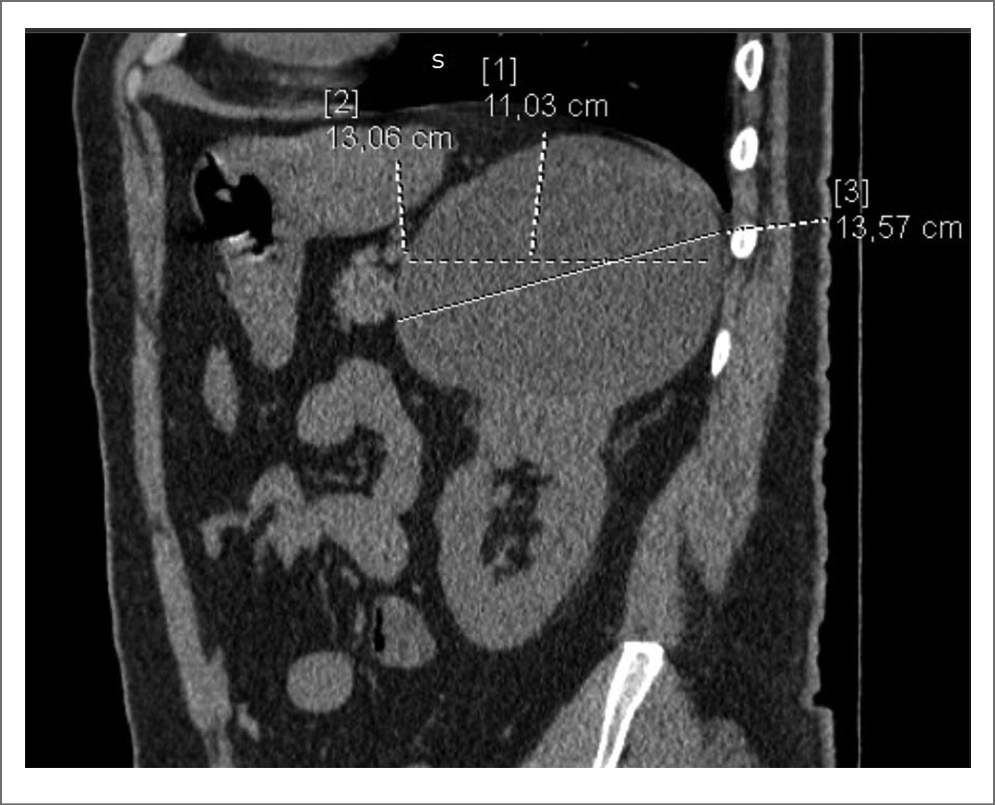

Стоит отметить клинический случай пациента из нашего исследования с кистой почки категории IIF диаметром до 131 мм в верхнем сегменте с тонкой капсулой и наличием пристеночного мягкотканного компонента, не накапливающего контраст. На рис. 1–4 представлены снимки мультиспиральной КТ пациента до операции с внутривенным контрастированием в различных срезах с демонстрационными измерениями. Выполнено оперативное вмешательство – лапароскопическое иссечение стенки кисты. В ходе операции после вскрытия стенки образования эвакуировано до 650 мл коричневой жидкости с желто-коричневыми хлопьями. При получении гистологического заключения верифицирован почечно-клеточный рак, проведена радикальная нефрэктомия в отсроченном порядке. Морфологическое исследование удаленной почки после повторного оперативного вмешательства подтвердило диагноз папиллярной карциномы, тип 2, G2 по Fuhrman. Т3N0M-R0.

Рис. 2. Киста левой почки. Сагиттальный срез. Нанесены измерения в максимальном размере образования.